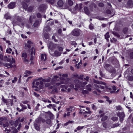

To deal with some of the aforementioned issues, we introduce a new approach for simultaneous H&E stain normalization and augmentation based on the multimarginal Wasserstein barycenter approach. Specifically, the novelty of the paper lies in first introducing the traditional Wasserstein barycenter approach for stain normalization/augmentation (Figure 1), and then introducing the multimarginal version [1, 9] to overcome the limitations of the traditional approach in this context (Figure 2). Note that the traditional Wasserstein barycenter (1 source and 1 reference), although widely employed in computer vision, to the best of our knowledge has never been used for stain normalization/augmentation and the more general multimarginal Wasserstein barycenter (1 source and multiple references) has hardly ever been used in computer vision or medical imaging communities. For more accurate stain normalization, the multimarginal version allows one to incorporate additional distributions by utilizing one or more intermediate reference images (Figure 2). The resultant interpolations span a broad spectrum of stain variations allowing for simultaneous stain normalization and augmentation.

We implemented our algorithm using the Python Optimal Transport (POT) library 222https://github.com/rflamary/POT which include GPU-accelerated versions of Sinkhorn regularization. We used Nvidia GeForce RTX 2080 Ti for our experiments. Pytorch framework was used for StainGAN 333https://github.com/xtarx/StainGAN and CNN3 444https://github.com/neerajkumarvaid/Nuclei_Segmentation implementations. We evaluated our approach against Reinhard et al. [12], Macenko et al.[7], Khan et al. [4], Vahadne et al. [17], and StainGAN [14].

4.1 Stain Normalization Evaluation

We used MITOS-ATYPIA’14 challenge dataset for evaluating our stain normalization. The dataset includes same tissue sections scanned by two different scanners (Aperio-A and Hamamatsu-H) with total 424 X20 A-H frame pairs, 300 training and 124 testing. Images from scanner A are normalized and matched against the real corresponding images from H (ground truth). As in StainGAN [14], 10,000 random (256256) patches from 300 training frames were used for training (26 epochs with the regularization parameter , learning rate 0.0002, Adam optimizer with a batch size of 4) and 500 patches from 124 testing data used for evaluation. The visual and quantitative comparisons are shown in Figure 3 and Table 1, respectively. For the traditional case (one reference and source), our results are very similar to Reinhard et al. [12] since they also do color matching in Lab space, but our results improve drastically given two reference images. The references in our case span patches with different amounts of background visible. We also tested with different reference images and we show that we get a tighter bound as long as the references contain different amounts of background visibility; see Figure 4 for the box plots of SSIM for different references.